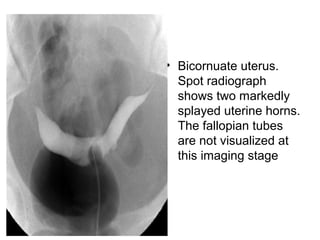

• Bicornuate uterus.

Spot radiograph

shows two markedly

splayed uterine horns.

The fallopian tubes

are not visualized at

this imaging stage

• Bicornuate uterus. Spotradiograph shows two markedly splayed uterine horns. The fallopian tubes are not visualized at this imaging stage